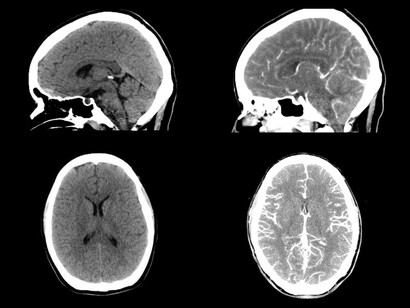

Es probable que también ordene análisis de sangre para detectar posibles causas subyacentes, como problemas de tiroides o hígado. Así como pruebas de neuroimagen (TAC o escáner, resonancia magnética nuclear y pruebas de medicina nuclear). Las pruebas de medicina nuclear rastrean el movimiento de dopamina en el cerebro y son conocidas de múltiples formas como SPECT, Datascan o DaT-SPECT y tomogammagrafía. La prueba utiliza marcadores radioactivos diseñados para rastrear la dopamina en el cerebro. Esto le permite al médico observar la liberación de este neurotransmisor en el cerebro de una persona e identificar las áreas cerebrales que la reciben o no atendiendo al brillo de dichas zonas.